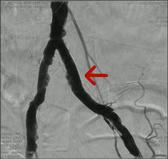

可怕的LEADDP 糖尿病下肢血管病变(LEADDP)可致患者肢体麻木、疼痛,间歇性跛行,乃至坏疽(糖尿病足),截肢率高达40 %以上。LEADDP是糖尿病致残、致死的主要原因,糖尿病患者因LEADDP造成的截肢,要比非糖尿病患者高5到10倍以上。先进的DSA + 微创介入 1、选择性血管造影(DSA)是LEADDP诊断的金标准。 2、微创介入治疗优点: 创伤小,仅有一2-3 mm的穿刺创口 成功率高:目前其成功率达85-90 % 保肢率高:术后病人截肢率可从40 %降为4 %左右 早发现早治疗:越早治疗效果越好.独创的微创介入 + HBO + bFGF综合治疗途径 1、DSA + 微创介入 2、高压氧(HBO)物理疗法:大型空气加压舱,治疗压力0.2 MPa,面罩吸纯氧30 min 3、基于重组成纤维细胞生长因子(bFGF)局部换药. |